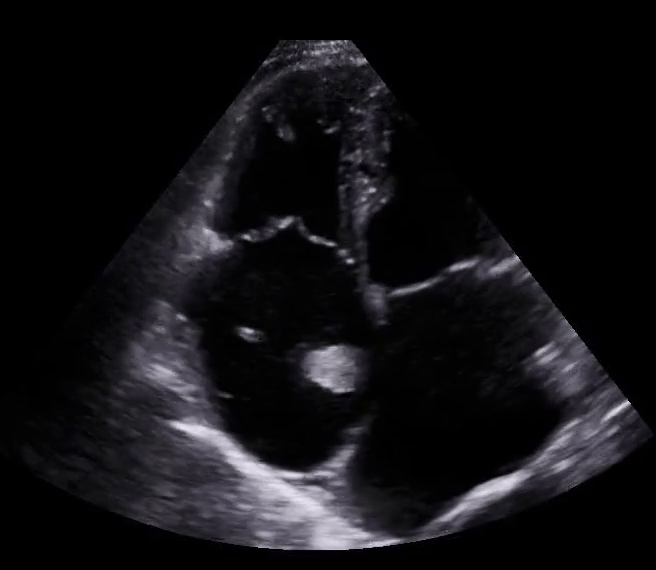

apical four chamber

Clip 3: Apical 4 Chamber: >1:1 RV/LV ratio. Of note, try to acquire this image with septal wall straight up and down in order to best evaluate chamber size. To improve this image the operator should swing their hand a little more laterally on patients chest.